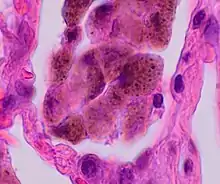

Comparison of pigmented pulmonary macrophages

| Disease | Macrophage name | Macrophage pigment appearance (HE stain) | Usual macrophage location | Associated medical history | Image | Image comment |

|---|---|---|---|---|---|---|

| Anthracosis | Black-brown granules | Interstitium (perivascular) |  |

Black arrow shows interstitial anthracotic pigment. Nearby macrophages (white arrow) can be presumed to contain anthracotic pigment. | ||

| Respiratory bronchiolitis | "Smoker’s macrophages" | Yellow to light brown and finely granular[4] | Airways (especially respiratory bronchioles) | Tobacco smoking |  |

Smoker's macrophage in center |

| Chronic pulmonary congestion | Siderophages | Brown-golden and refractile.[5] | Alveoli[6] |

|

|

Siderophage (black arrow), and interstitium with edema, hemosiderin deposition (black arrow) and collagenous thickening, indicating heart failure. |